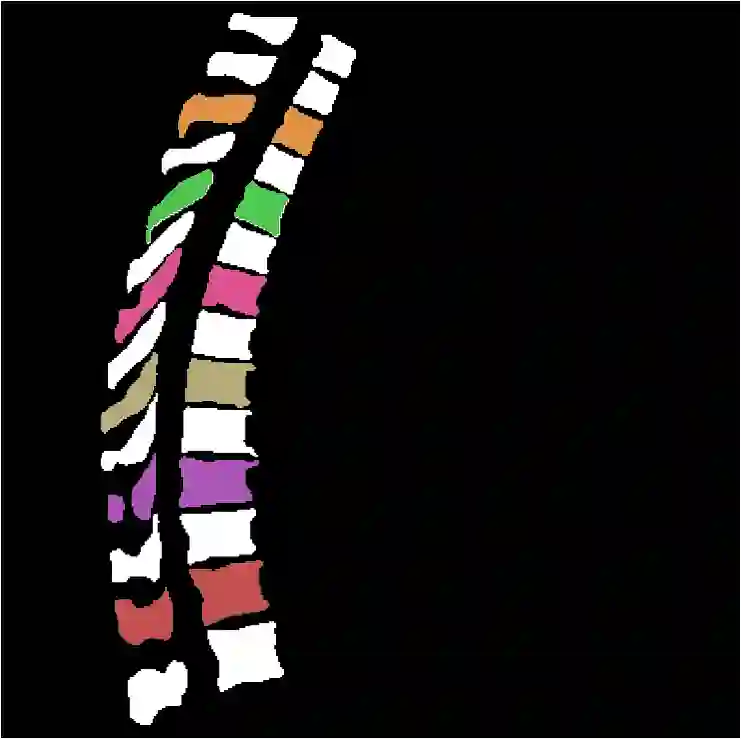

Vertebrae localization, segmentation and identification in CT images is key to numerous clinical applications. While deep learning strategies have brought to this field significant improvements over recent years, transitional and pathological vertebrae are still plaguing most existing approaches as a consequence of their poor representation in training datasets. Alternatively, proposed non-learning based methods take benefit of prior knowledge to handle such particular cases. In this work we propose to combine both strategies. To this purpose we introduce an iterative cycle in which individual vertebrae are recursively localized, segmented and identified using deep-networks, while anatomic consistency is enforced using statistical priors. In this strategy, the transitional vertebrae identification is handled by encoding their configurations in a graphical model that aggregates local deep-network predictions into an anatomically consistent final result. Our approach achieves state-of-the-art results on the VerSe20 challenge benchmark, and outperforms all methods on transitional vertebrae as well as the generalization to the VerSe19 challenge benchmark. Furthermore, our method can detect and report inconsistent spine regions that do not satisfy the anatomic consistency priors. Our code and model are openly available for research purposes.